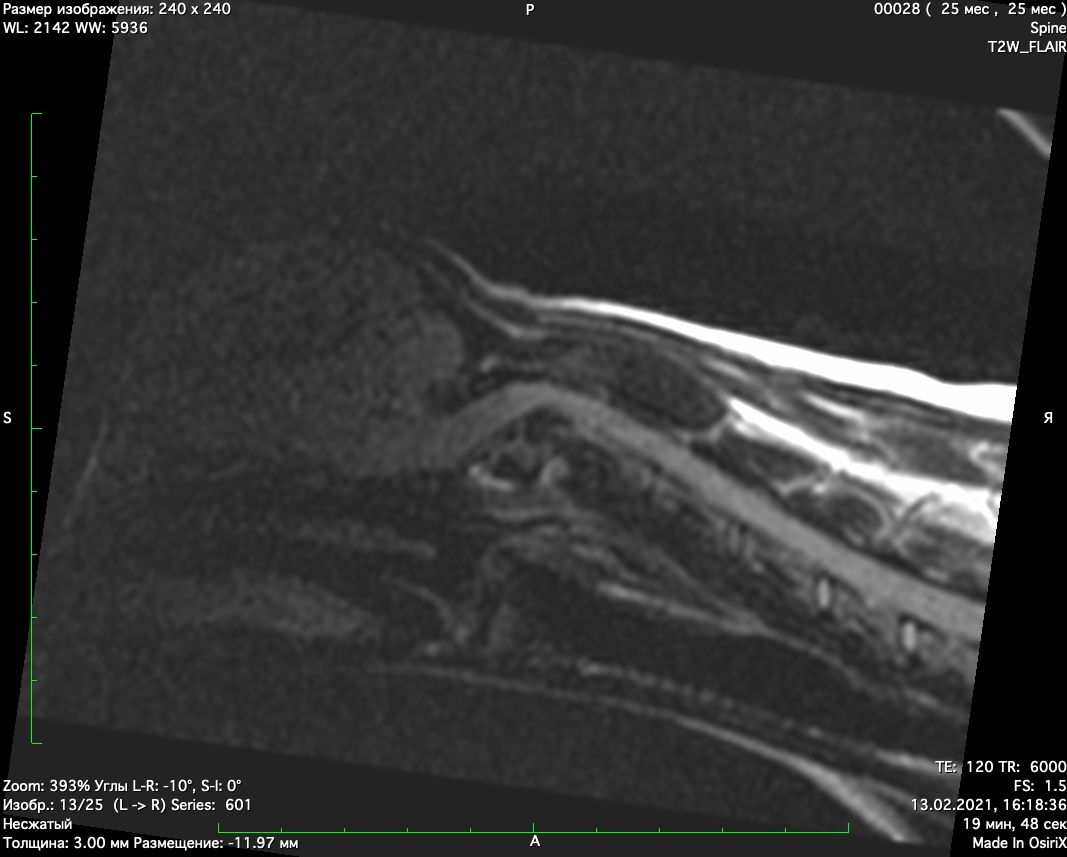

При проведении мрт диагностики установлено смещение второго шейного позвонка с компрессией спинного мозга, аплазия зуба второго шейного позвонка